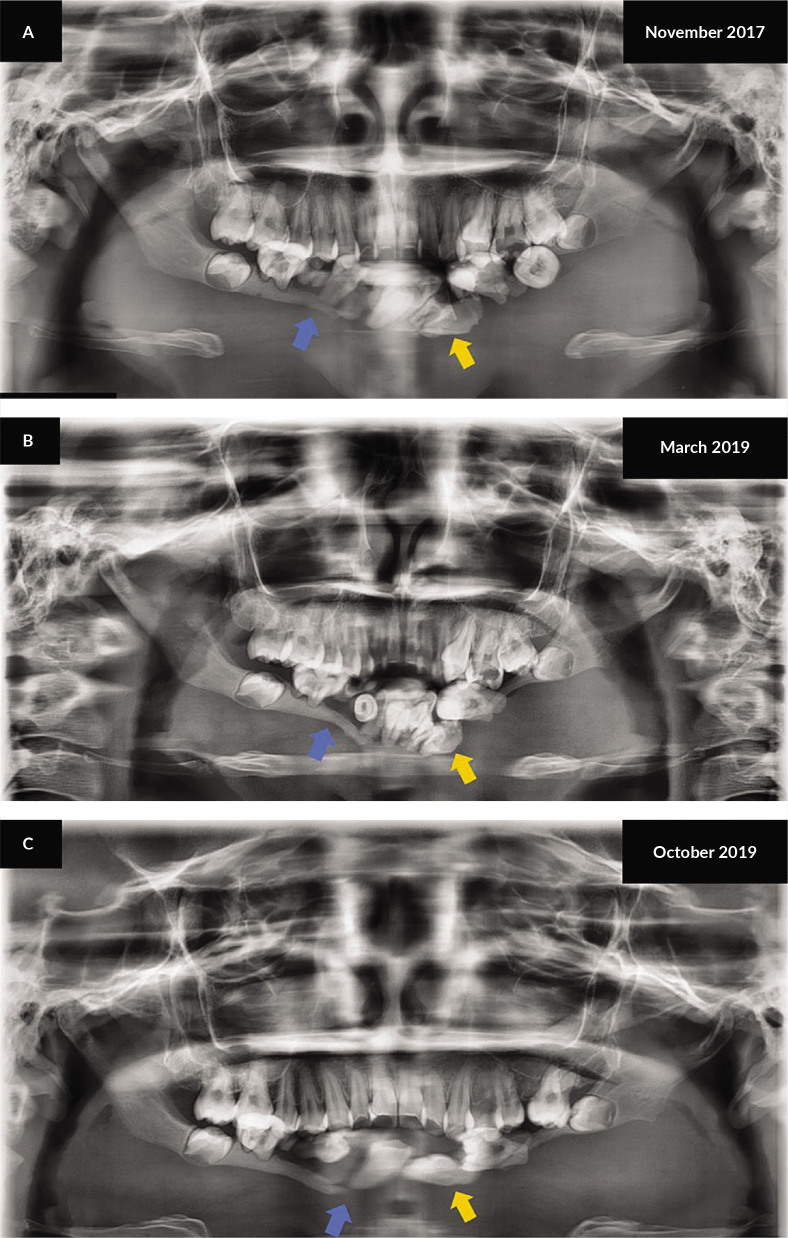

Gorham-Stout病是一种罕见的溶骨性疾病,其病理生理机制尚不清楚。它表现为以骨基质丧失和畸形血管增生为特征的病变。目前,没有金标准的诊断评估方案,它是通过临床、组织病理学和放射学结果的混合诊断的。我们报告一个19岁的女性与Gorham-Stout病表现为8年进行性软组织肿块在下颌骨。广泛的骨溶解下颌骨与集群的下颌牙列是注意到在计算机断层扫描(CT)成像。她的病例在一个多学科会议上讨论,她的治疗是放疗后手术±重建。我们使用基于ct的三维规划技术,在20个疗程中对相关区域给予40 Gy的治疗。治疗后,6周复查CT以重新评估疾病进展或稳定,然后进行手术切除。截至2021年10月31日,治疗后48个月无复发迹象。对Gorham-Stout病的明确诊断具有挑战性,多学科团队方法可以帮助确定具有最佳结果的治疗选择。

Gorham-Stout disease is a rare osteolytic disorder with an unclear pathophysiology. It presents as lesions characterized by the loss of the bony matrix and the proliferation of malformed vasculature. At present, there are no gold-standard diagnostic evaluation protocols and it is diagnosed through a mixture of clinical, histopathologic, and radiographic findings. We report a case of a 19-year-old female with Gorham-Stout disease presenting with an 8-year progressive soft tissue mass in the mandible. Extensive osteolysis of the mandible with clustering of the mandibular dentition is noted on computed tomography (CT) imaging. Her case was discussed in a multidisciplinary conference and her treatment was radiotherapy followed by surgery ± reconstruction. We used a CT-based three-dimensional planning technique to give 40 Gy over 20 treatment sessions to the involved areas. Post treatment, a repeat CT was done at six weeks to reassess for disease progression or stabilization, followed by surgical excision. As of 31 October 2021, no evidence of recurrence is noted 48 months after treatment. Arriving at a definitive diagnosis with Gorham-Stout disease is challenging and a multidisciplinary team approach can help determine the treatment choice with best outcomes.